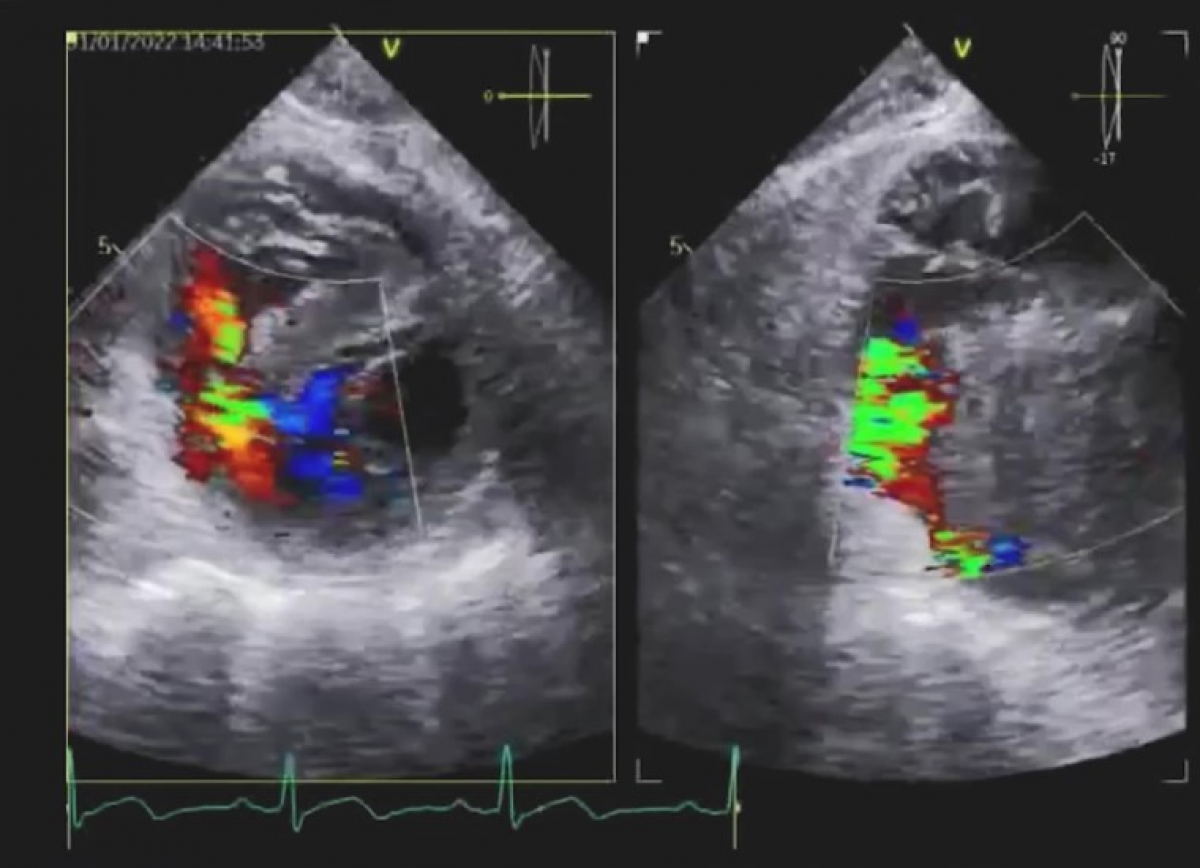

Pacjentka z ostrym zawałem mięśnia sercowego z uniesieniem odcinka ST.

Powikłanie mechaniczne zawału - pęknięcie przegrody międzykomorowej. Ciężkie zwężenie zastawki aortalnej.

Echokardiografia przezklatkowa i przezprzełykowa

Echokardiografia trójwymiarowa.

Ocena nabytego ubytku w przegrodzie międzykomorowej.